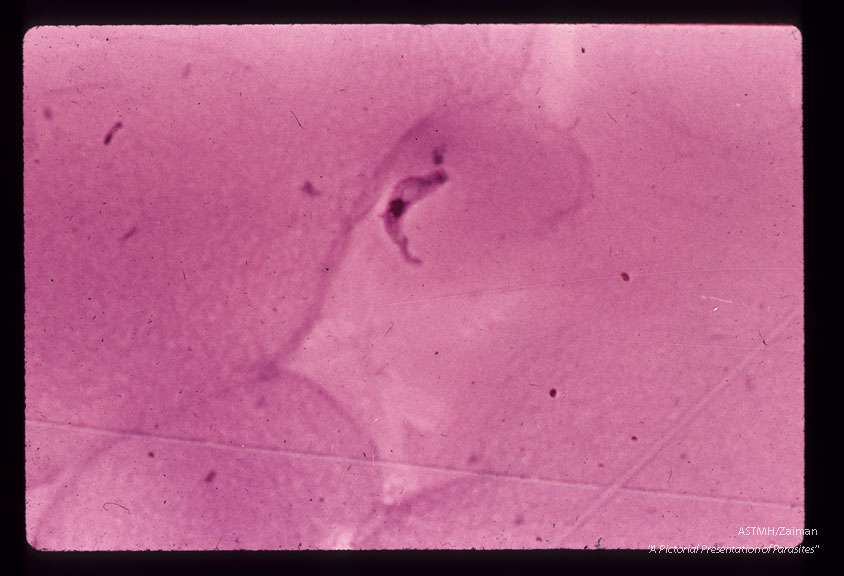

A seventy-one year old white male,  with a history of malaria 40 years earlier,  complained of weakness of three weeks duration following a vacation trip through Botswana,  South Africa in July and August of 1971.    During that trip he suffered many insect bites.    In September because of malaise,  chills and fever,  he started taking quinine.    A local physician subsequently prescribed quinine and Daraprim.    The chills and fever abated but weakness persisted. He became anorectic and lost weight. Physical examination in New York (Dr.  Hoskins) was remarkable for lethargy,   mild cnoephalopathy on HIP testing but no localizing signs,  bilateral,  cervical,  axilary and inguinal lymphadenopathy. Laboratory examination revealed slight anemia,  and motile trypanosomes in the; peripheral blood     The spinal fluid was clear,  opening pressure 130mm.   H2O,  4RBC,   33WBC, 84% mono,   16% sugar,   58% protein.    Twenty eight motile trypanosomes   / mm3 were seen in the counting chamber. The patient was treated with Suramin and Mel B (Arsobal) . The parasitemia disappeared,  the CSF cleared.    The patient probably suffered a transient reaction to Mel B (AS1)   with muscle weakness,  proximal more than distal with decreasing vibratory sense and fine tremor.  In spinal fluid of same patient.

Trypanosoma rhodesiense

Description: A seventy-one year old white male, with a history of malaria 40 years earlier, complained of weakness of three weeks duration following a vacation trip through Botswana, South Africa in July and August of 1971. During that trip he suffered many insect bites. In September because of malaise, chills and fever, he started taking quinine. A local physician subsequently prescribed quinine and Daraprim. The chills and fever abated but weakness persisted. He became anorectic and lost weight. Physical examination in New York (Dr. Hoskins) was remarkable for lethargy, mild cnoephalopathy on HIP testing but no localizing signs, bilateral, cervical, axilary and inguinal lymphadenopathy. Laboratory examination revealed slight anemia, and motile trypanosomes in the; peripheral blood The spinal fluid was clear, opening pressure 130mm. H2O, 4RBC, 33WBC, 84% mono, 16% sugar, 58% protein. Twenty eight motile trypanosomes / mm3 were seen in the counting chamber. The patient was treated with Suramin and Mel B (Arsobal) . The parasitemia disappeared, the CSF cleared. The patient probably suffered a transient reaction to Mel B (AS1) with muscle weakness, proximal more than distal with decreasing vibratory sense and fine tremor. In spinal fluid of same patient.